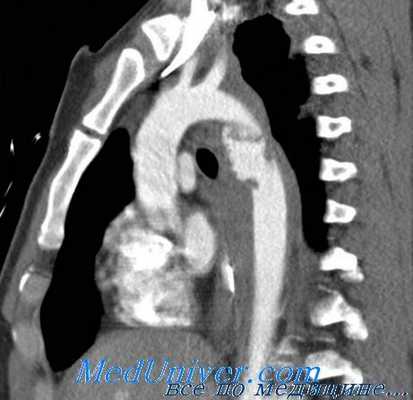

протезирование (а) и малоинвазивное стентирование (б) аорты